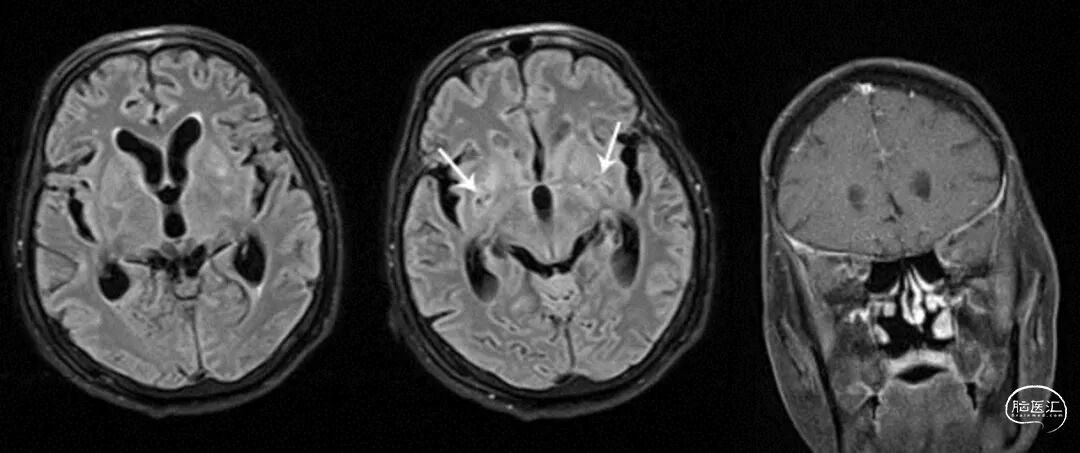

然而,对于免疫力较低的人(如HIV感染者、器官移植者),它可能趁虚而入,引起严重的隐球菌性脑膜炎。这种病起病较慢,症状包括持续头痛、发烧、恶心呕吐等,容易被忽略。

治疗中一个非常关键的措施是管理颅内高压,医生需要通过多次腰穿释放脑脊液来降低压力,这直接关系到治疗的成败。

直接做脑室腹腔分流治疗急性脑积水,也值得试一试。总之,此病重在早发现、规范足疗程治疗和精细的并发症管理。